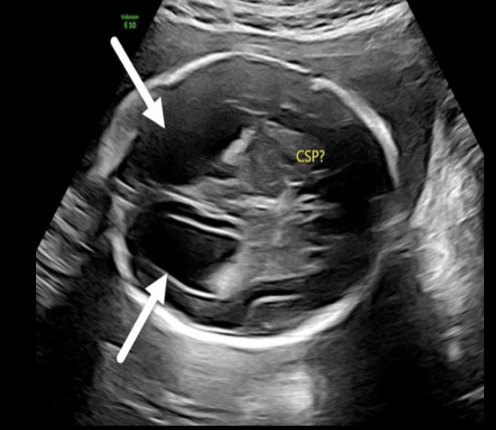

absent cavum septum pellucidum + septop-optic dysplasia are common findings in

.

a) dandy walker malformation + lissencephaly

b) cerebellar agenesis + dandy walker malformation

c) holoprosencephaly + schizencephaly

d) holoprosencephaly + dandy walker malformation

septo-optic dysplasia = mild form of lobar holoprosencephaly

* absent cavum septum pellucidum + optic nerve hypoplasia